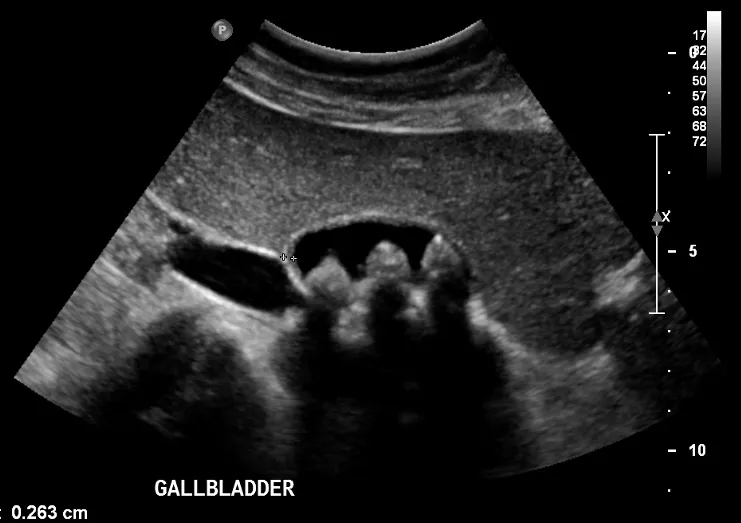

- Diagnosis: Abdominal ultrasound is the gold standard imaging test.

- Dx: RUQ ultrasound shows thickened wall (>4 mm), pericholecystic fluid. Positive Murphy's sign.